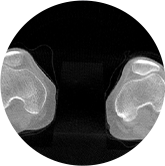

髖關節

膝關節

關閉金屬偽影校正

開啟金屬偽影校正